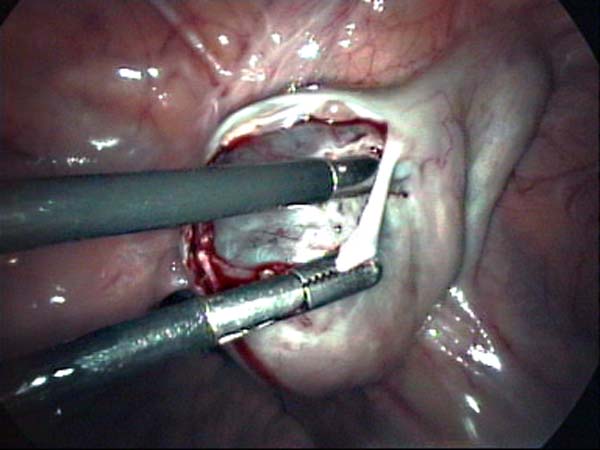

Photos laparoscopie Kyste ovarien Cystectomie ovarienne Septum utérin Grossesse tubaire